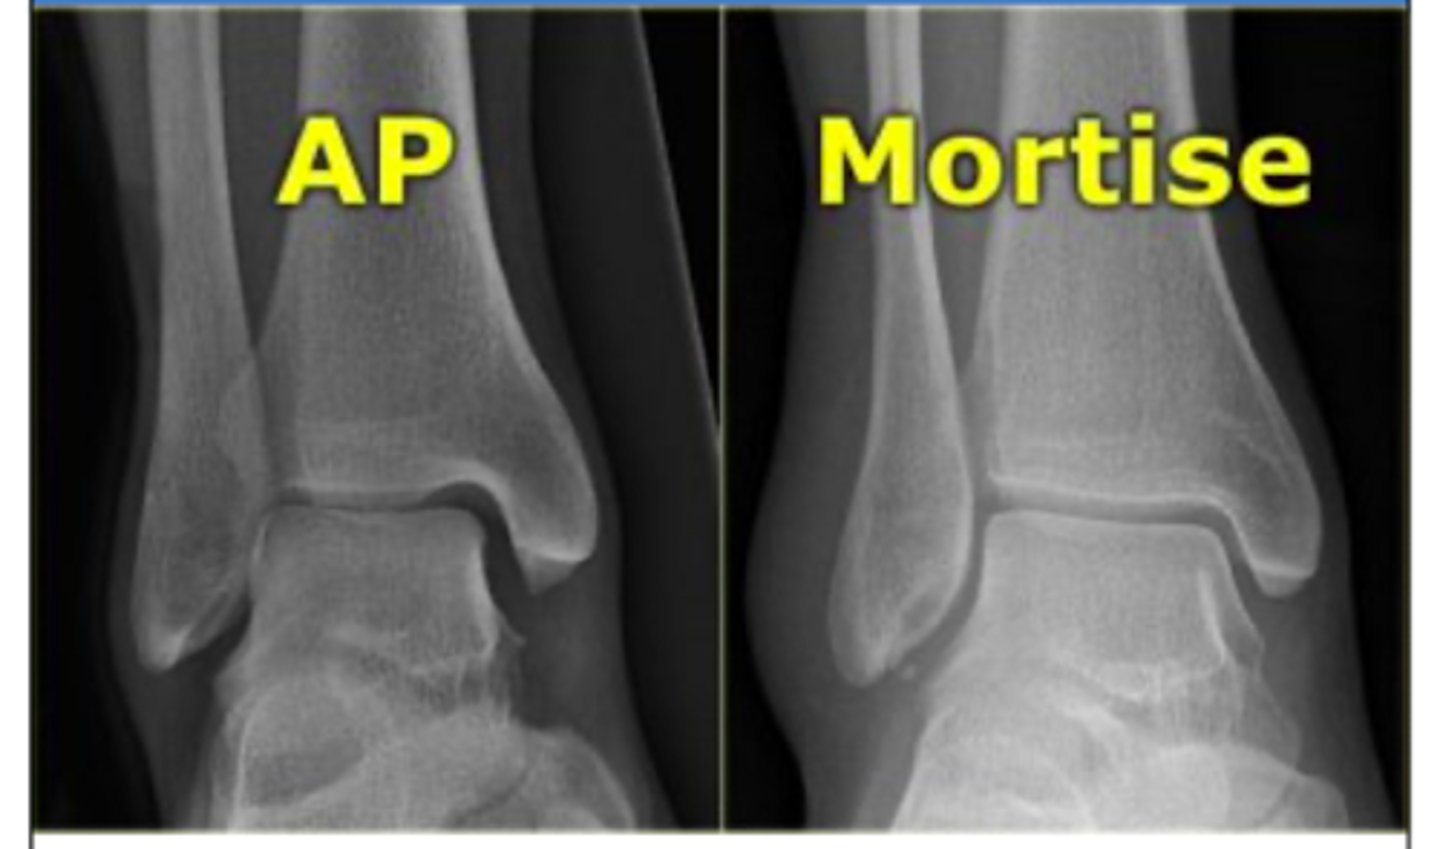

AP vs. Mortise ankle view?

AP → lateral malleolus will overlap

Mortise → no overlap; will show the mortise joint space (lateral)

What does a medial clear space of >6mm indicate? What is a normal length?

indicates disruption of the medial collateral ligament

- should be <4mm

A lateral clear space of >1cm indicates what?

syndesmotic rupture (distal tibiofibular ligament rupture)